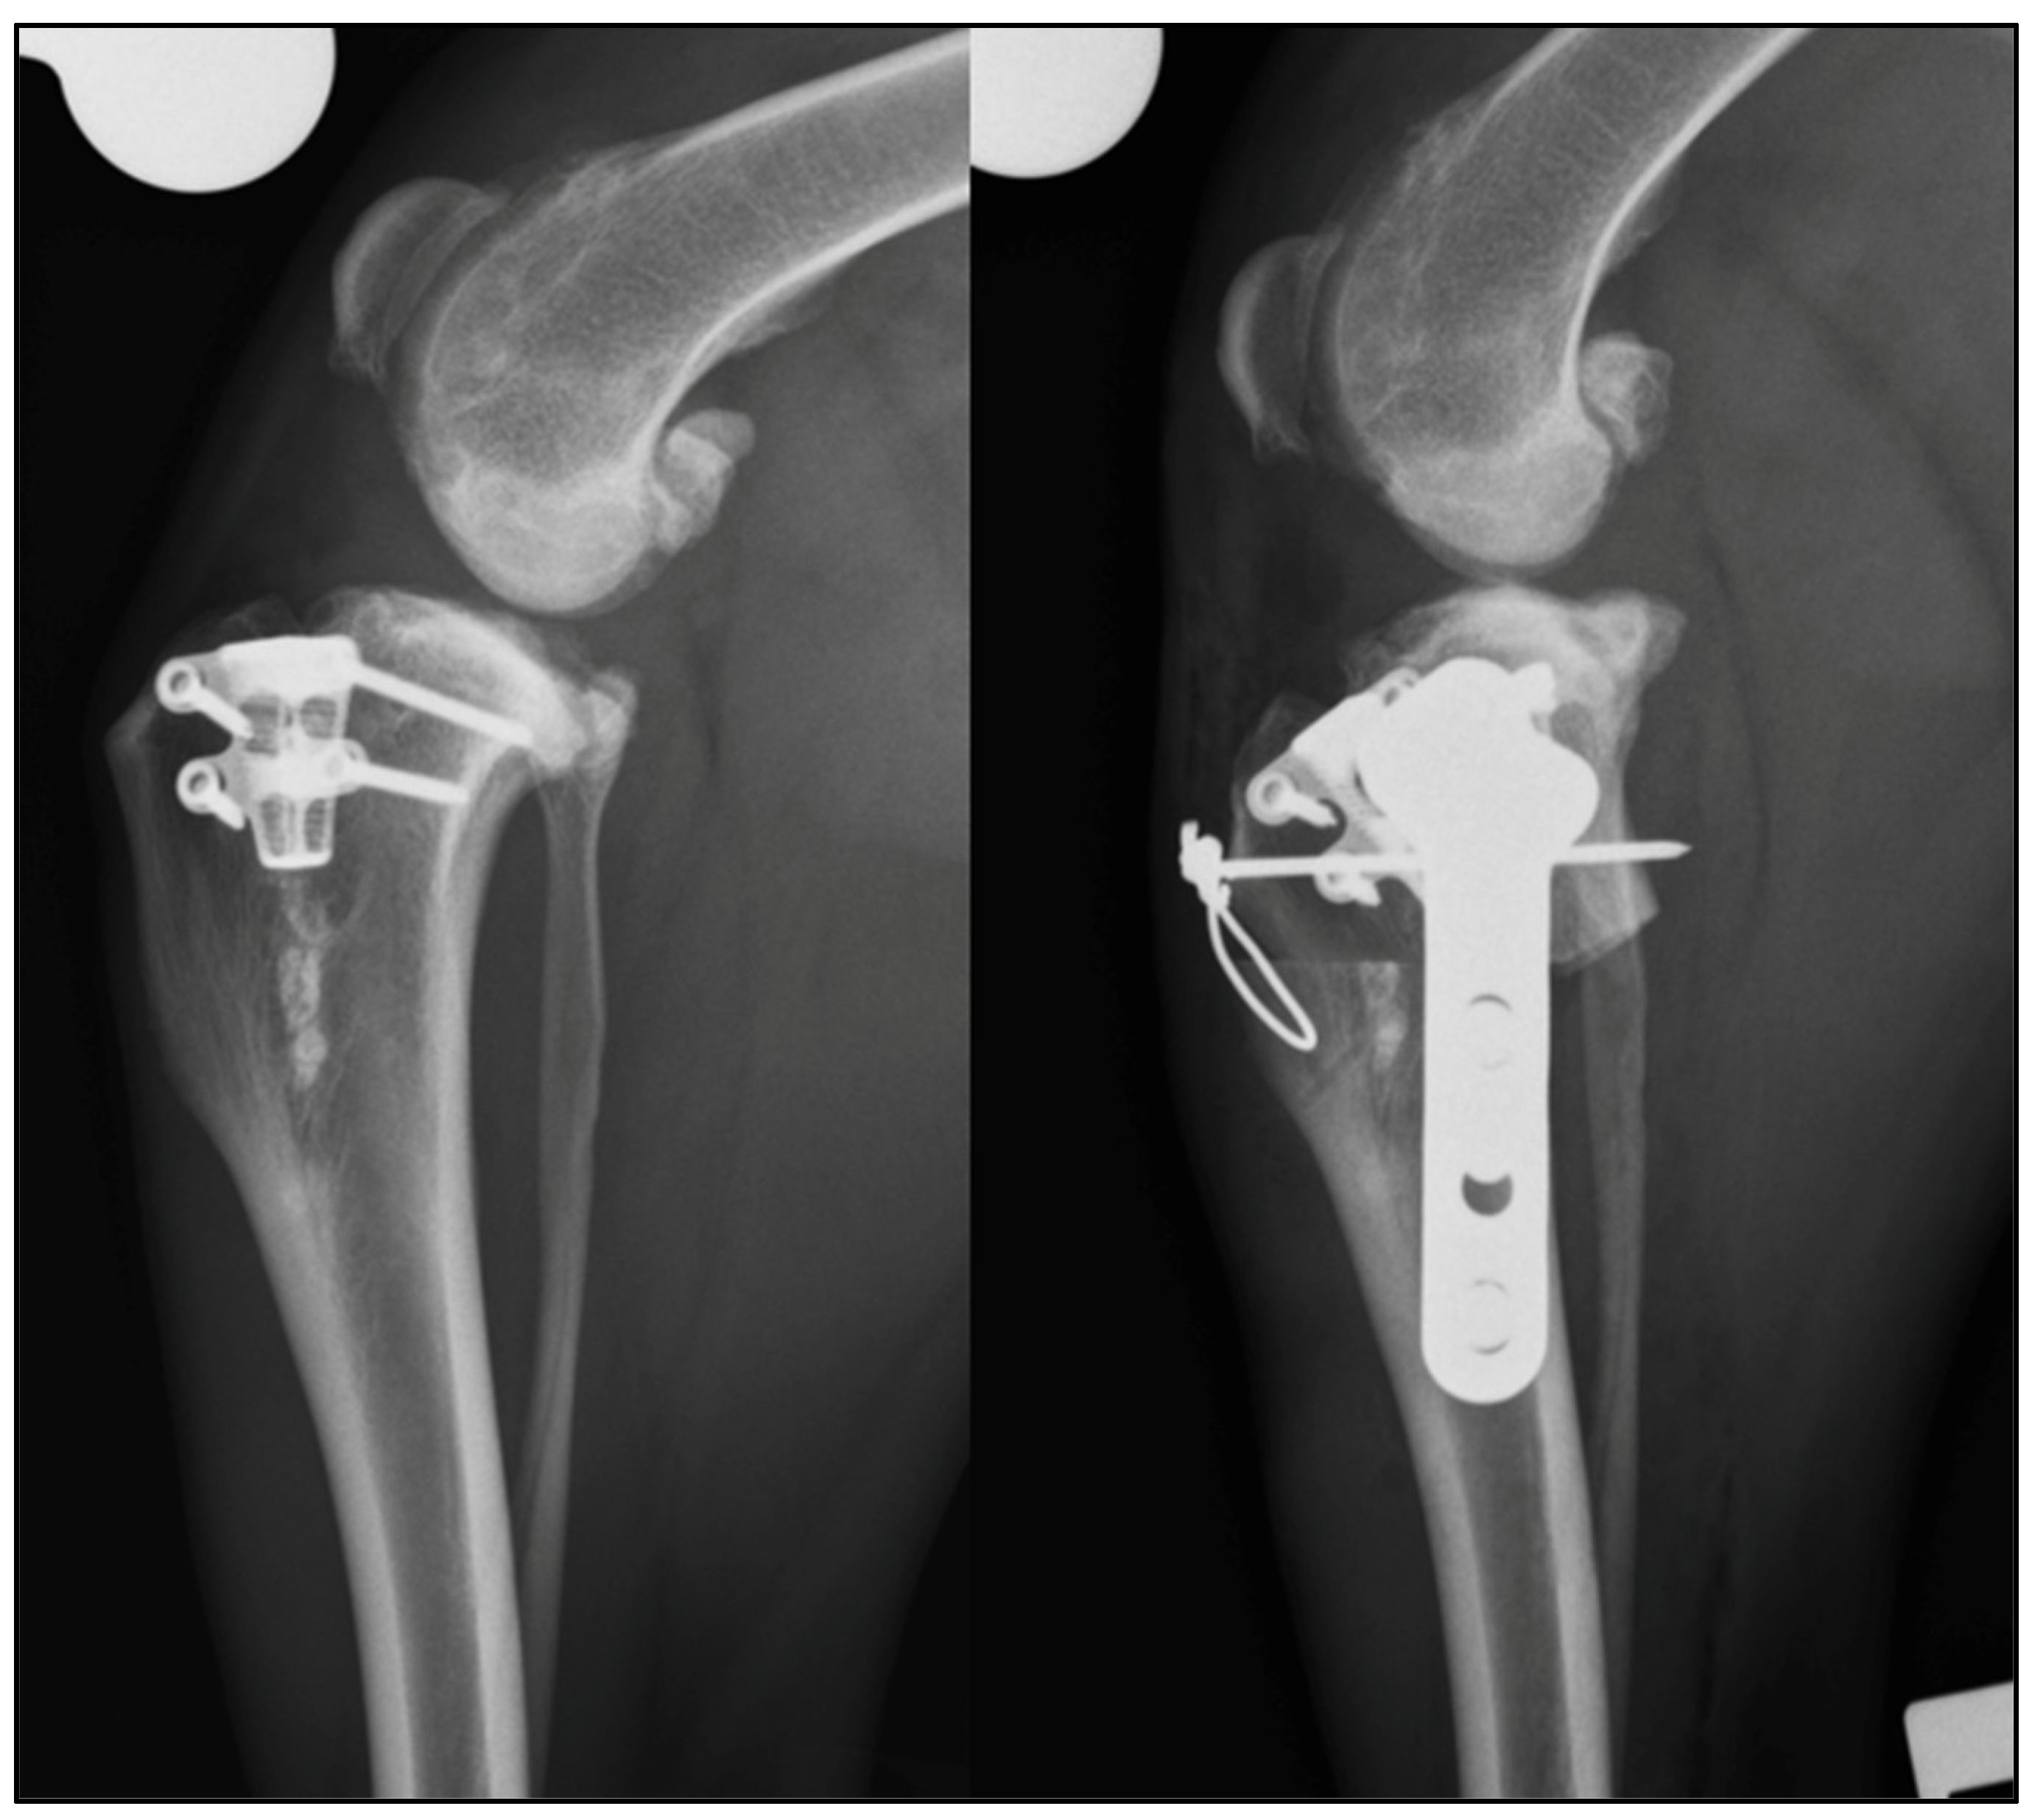

| 1 | Modified Maquet tibial tuberosity advancement | 104° | 94 ° | 28° | TPLO | Complete CCL rupture, intact menisci | 109° | 77° | 9° |

| 2 | TTA rapid | 112° | 96° | 32° | Modified CCWO (mCCWO) | Complete CCL rupture and medial meniscal tear (caudal horn) | 129° | 87° | 0° |

| 3 | Modified Maquet Procedure (MMP) | 104° | 90° | 24° | TPLO | Partial CCL rupture and intact menisci | 105° | 74° | 4° |

| 4 | MMP | 108° | 96° | 26° | TPLO and tension band | N/A | 106° | 86° | 9° |

| 5 | MMP | 137° | 102° | 34° | TPLO and tension band | N/A | 117 ° | 79° | 4° |

| 6 | MMP with 2 staples | 111° | 95° | 27° | TPLO | N/A | 115° | 79° | 8° |

| 7 | Modified Maquet Technique (MMT) | 108° | 83° | 22° | TPLO | Complete CCL rupture and medial meniscal tear (cranial horn) | 127° | 70° | 1° |